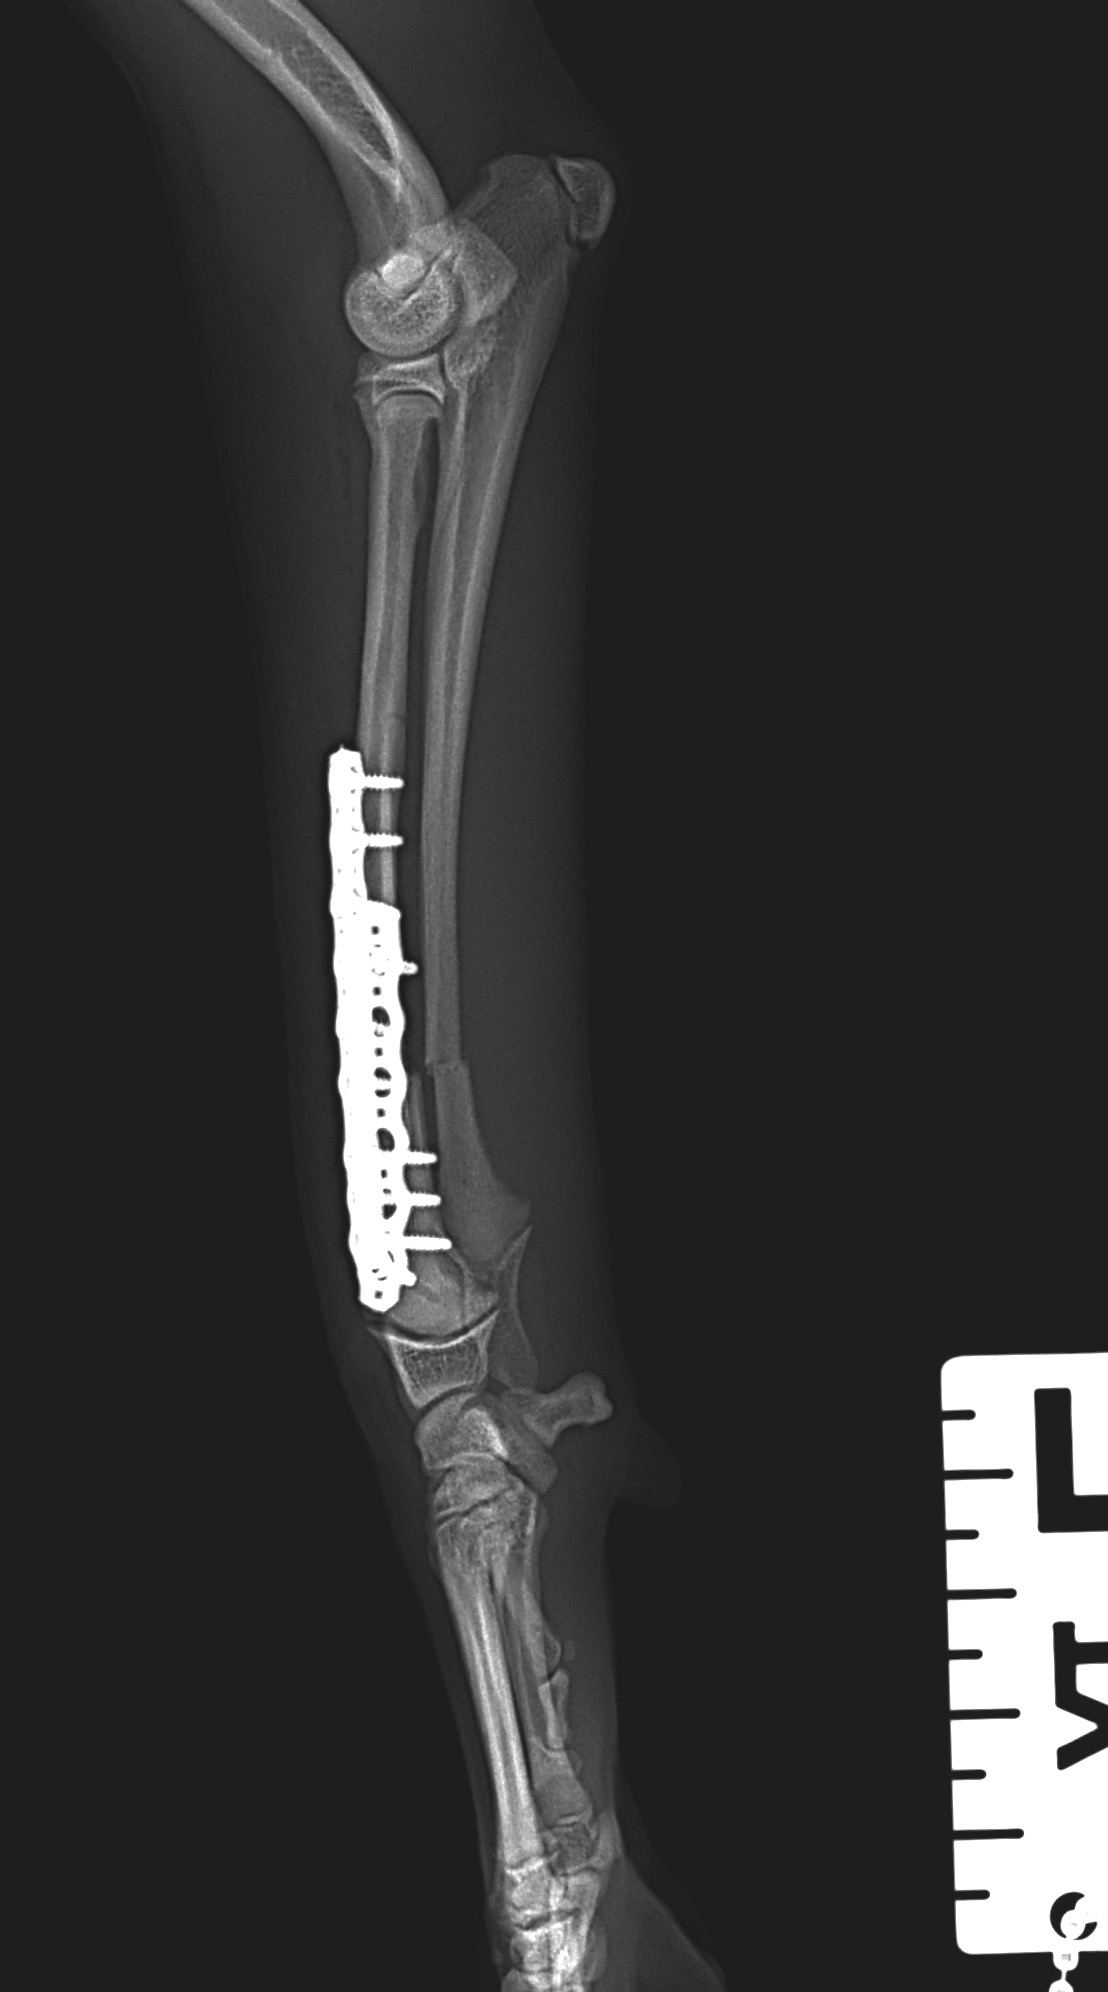

5ヶ月齢の小型犬がソファーからジャンプしたのちに橈骨骨折をしたとの事で、かかりつけ医より紹介受診されました。橈骨は遠位で階段状斜骨折を呈していました。遠位3穴にデザインされたストレートの1.5 Locking Plateをメインとし、橈骨の内側面からOrthogonal Plateにより骨接合術を行いました。しばらくは安静が必要です。